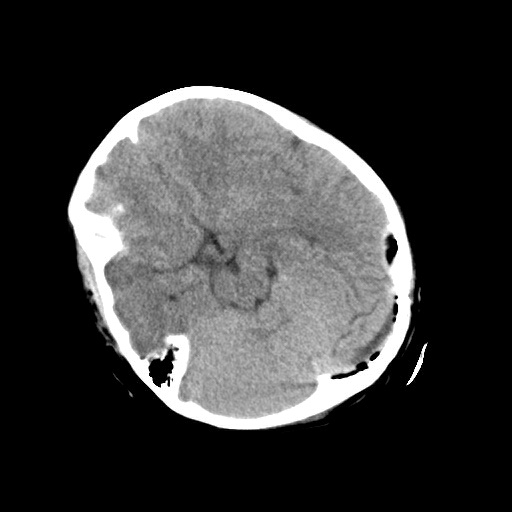

▲术后复查

目前小景生命体征平稳,在神经外科医护人员的保驾护航下,恢复良好,未出现神经功能缺损症状。